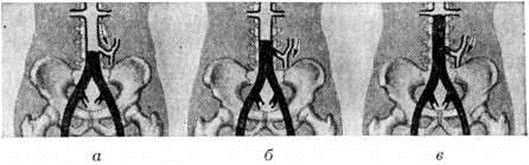

Лериша синдромЛериша синдром (R. Leriche, французский хирург, 1879—1955; синонимы: хроническая закупорка аорты, атеросклеротический тромбоз брюшной аорты, аортоподвздошная окклюзия) — совокупность клинических проявлений, обусловленных хронической окклюзией бифуркации брюшной аорты и подвздошных артерий. Р. Лериш в 1940 год выполнил первую поясничную симпатэктомию и резекцию тромбированной бифуркации брюшной аорты. С 1943 год по предложению Мореля (F. Morel) этот симптомокомплекс стал называться «синдром Лериша». У мужчин заболевание наблюдается в 10 раз чаще. Наиболее часто заболевание отмечается у лиц в возрасте 40—60 лет. Этиология разнообразна. Наблюдаются как врождённые, так и приобретённые окклюзии аортоподвздошного отдела сосудистого русла. К числу врождённых заболеваний относится гипоплазия аорты и фиброзно-мышечная дисплазия подвздошных артерий. Из приобретённых заболеваний наиболее частой причиной является атеросклеротическое поражение (88—94%), неспецифический аортоартериит (5—10%), значительно реже постэмболические тромбозы и другие Патогенез нарушения кровообращения обусловлен степенью и протяжённостью окклюзии аорты и подвздошных артерий, что резко уменьшает объем кровотока в органы таза и нижние конечности. Поэтому на первых этапах заболевания ишемия (смотри полный свод знаний) проявляется во время функциональный нагрузки, а при прогрессировании процесса и в покое. Ведущим проявлением заболевания является снижение перфузионного давления в дистальном сосудистом русле и нарушение микроциркуляции (смотри полный свод знаний), а затем и обменных процессов в тканях. В характере компенсации нарушений гемодинамики большое значение имеет развитие коллатерального кровообращения. Патологическая анатомия зависит от этиологии поражения. Обнаруживаются характерные для атеросклероза изменения аорты (смотри полный свод знаний Атеросклероз). Максимальные изменения наблюдаются в области бифуркации аорты и в месте отхождения внутренней подвздошной артерии. Часто имеется выраженный кальциноз стенки аорты и артерии (смотри полный свод знаний Кальциноз), во многих случаях — пристеночный тромбоз (смотри полный свод знаний). Гистологический картина атеросклеротического поражения не имеет особенностей. При неспецифическом аортоартериите в первую очередь поражается также аорта. Для этого заболевания характерен выраженный перипроцесс, резкое утолщение стенки аорты за счёт воспаления наружной, средней и реактивного утолщения внутренней оболочки. Нередко отмечается кальциноз стенки. Клиническая картина зависит от протяжённости поражения сосудистого русла и степени развития коллатерального кровообращения. В зависимости от проксимального уровня окклюзии брюшной аорты выделяют 3 варианта Лериша синдром (рисунок 1): низкая окклюзия (А) — дистальнее нижней брыжеечной артерии; средняя окклюзия (Б) — проксимальнее нижней брыжеечной артерии и высокая окклюзия (В) — сразу дистальнее или на уровне почечных артерий. В зависимости от поражения дистального сосудистого русла целесообразно выделять 4 типа (рисунок 2): I тип — поражение аорты и общих подвздошных артерий; тип — поражение аорты, общих и наружных подвздошных артерий; тип — к изменениям при II типе присоединяется поражение поверхностной бедренной артерии; IV тип— дополнительно поражены сосуды голени. При всех типах поражения дистального сосудистого русла выделяется вариант «а» — с проходимой глубокой артерией бедра и вариант «б» — имеется стеноз или окклюзия устья этой артерии. Следует отметить, что при этом имеется в виду не только окклюзия (полная облитерация) сосуда, но и резкие стенозы (более 75% диаметра). Поражение дистального сосудистого русла у одного и того же больного может быть асимметричным. Различают 4 степени ишемии: I — начальные проявления; IIA — появление перемежающейся хромоты через 300—500 метров ходьбы; II Б — появление перемежающейся хромоты через 200 метров ходьбы; III — боли через 25— 50 метров ходьбы или в покое; IV — наличие язвенно-некротических изменений. Первым симптомом заболевания обычно являются боли, которые появляются в икроножных мышцах при ходьбе. Практически 90% больных с Лериша синдром обращаются к врачу по поводу перемежающейся хромоты (смотри полный свод знаний). |